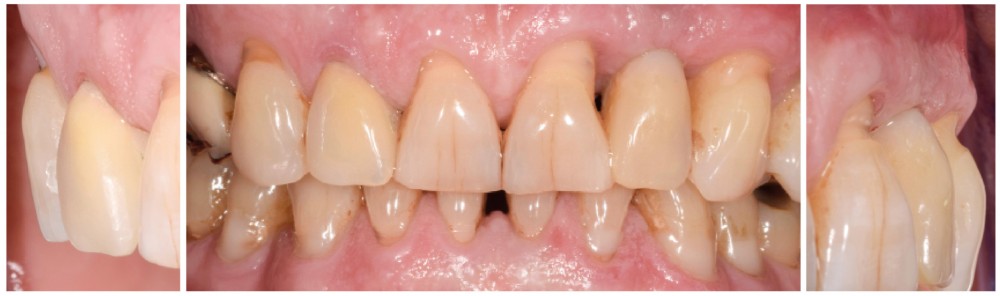

Un patient de 62 ans se présente en consultation afin de réaliser les coiffes prothétiques des dents 12 et 22. La 12 présente une restauration par prothèse transitoire non adaptée. Un implant au niveau de la 22 a été posé par un autre praticien selon une technique chirurgicale en deux temps. Le praticien a adressé le patient pour la réalisation prothétique. L’option de bridge collé cantilever mono ailette n’avait pas été retenue ou proposée selon une technique chirurgicale en deux temps. Le patient souhaite rétablir l’esthétique et la fonction de ces deux dents uniquement.

Au vu des conditions initiales, il nous apparaît impossible de restaurer une esthétique satisfaisante, notamment au niveau de l’alignement des collets, sans une chirurgie muco-gingivale associée à une réhabilitation des dents antérieures par facettes. En effet, la perte de la 22, associée à une forme triangulaire des dents, a provoqué un non-alignement des collets ainsi que la présence de trous noirs entre les dents 21-22 et 22-23. Cependant, les contraintes exprimées par le patient contre-indiquaient ce traitement.